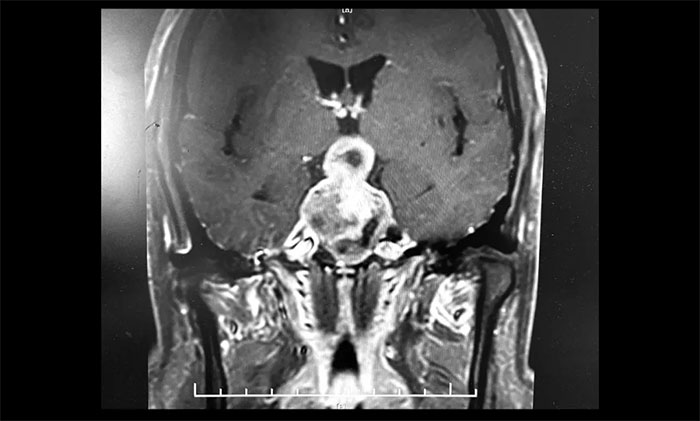

▲ 5公分巨大垂體瘤,呈“啞鈴”形,李士其教授團(tuán)隊迎難而上順利切除

李士其教授分析,對于病變已經(jīng)侵襲海綿竇,單純采用以往經(jīng)鼻入路或經(jīng)顱入路的術(shù)式均難以全切腫瘤,并且頸內(nèi)動脈損傷的風(fēng)險極大。如何將頸內(nèi)動脈損傷風(fēng)險降到最低,又能盡可能全切腫瘤?一般考慮采用經(jīng)蝶和經(jīng)顱聯(lián)合入路手術(shù)策略切除腫瘤。

目前聯(lián)合入路切除垂體瘤通常有兩種方式,一是采用聯(lián)合入路一次手術(shù)實現(xiàn)腫瘤全切除,二是分次手術(shù)以達(dá)到腫瘤切除的目的。李士其教授介紹,此類手術(shù),對患者的視力保護(hù)極其重要,對于巨大垂體瘤難以一次性手術(shù)切除的腫瘤,可以先行一次手術(shù),然后在數(shù)周或數(shù)月后執(zhí)行進(jìn)行二次手術(shù),即經(jīng)蝶和經(jīng)顱聯(lián)合入路分次手術(shù)策略。

李士其教授指出,因腫瘤組織多數(shù)較軟,鞍內(nèi)減壓后,鞍上及海綿竇內(nèi)腫瘤?上虬皟(nèi)塌陷。如術(shù)中塌陷不滿意可暫予觀察,一般1-3月后復(fù)查腫瘤可大部落入鞍內(nèi),可再次經(jīng)蝶手術(shù)進(jìn)一步切除。如仍不塌陷可考慮開顱手術(shù),此時開顱手術(shù)難度及風(fēng)險降低,而鞍底組織已愈合,一般不必?fù)?dān)心腦脊液漏。